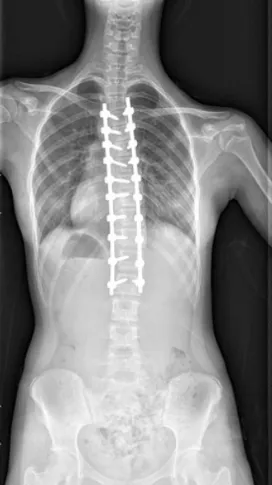

▲ 女,12岁,特发性脊柱侧凸、先天性脊柱畸形